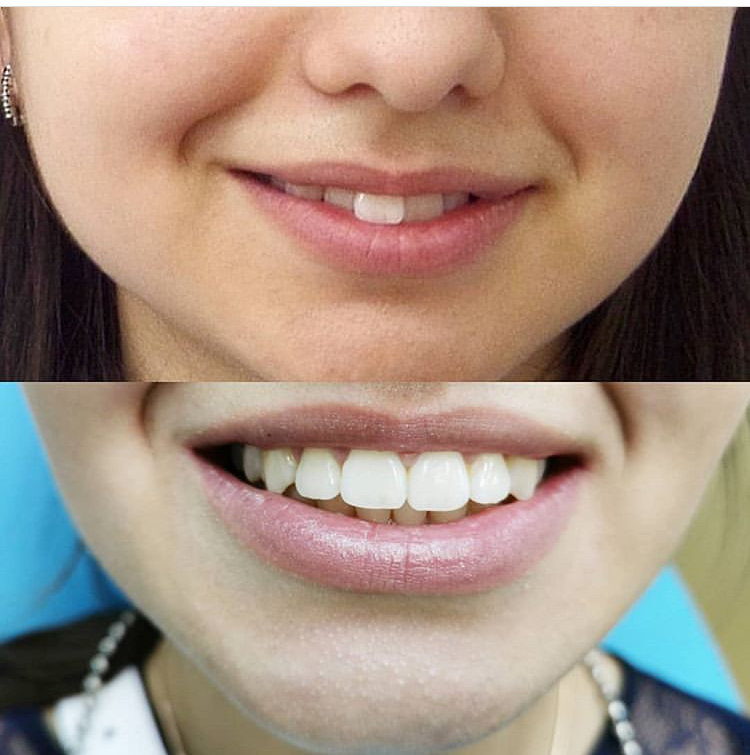

Улыбка звезды: крупный план фотографий передних зубов

Раздел: Фотодневник открытий